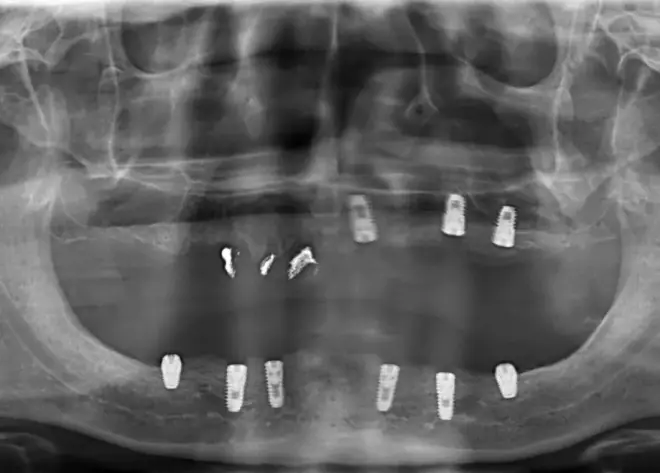

经过一番检查,江文彬医生发现阎叔叔的口腔情况非常糟糕,因为长期佩戴假牙的原因,导致牙槽骨被严重吸收,骨量不足,导致种牙非常困难。万幸的是,骨增量种植技术也是江文彬医生的拿手好戏。根据这位叔叔的牙周以及牙槽骨情况,最终江文彬医生为这位叔叔定制了全智能精控骨增量种植方案,在其上下颌各植入4颗植体,最终为这位戴了多年活动假牙的叔叔成功修复了全口牙。